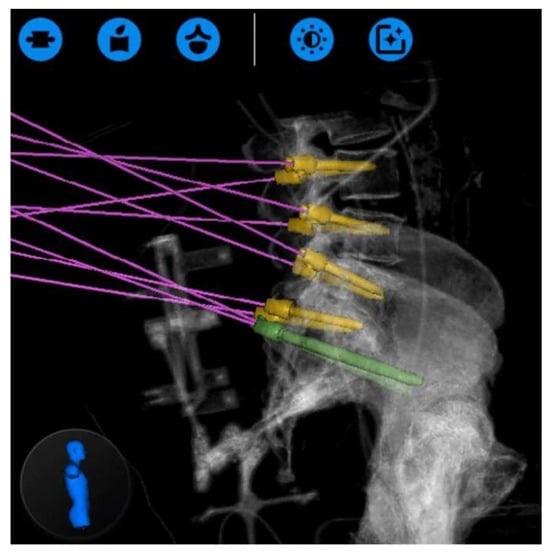

- Dalton, T.; Sykes, D.; Wang, T.Y.; Donnelly, D.; Than, K.D.; Karikari, I.O.; Goodwin, C.R.; Gupta, D.K.; Wiggins, W.F.; Abd-El-Barr, M.M. Robotic-Assisted Trajectory Into Kambin’s Triangle During Percutaneous Transforaminal Lumbar Interbody Fusion-Initial Case Series Investigating Safety and Efficacy. Oper. Neurosurg. 2021, 21, 400–408. [Google Scholar] [CrossRef] [PubMed]

- Park, C.; Crutcher, C.; Mehta, V.A.; Wang, T.Y.; Than, K.D.; Karikari, I.O.; Goodwin, C.R.; Abd-El-Barr, M.M. Robotic-assisted percutaneous iliac screw fixation for destructive lumbosacral metastatic lesions: An early single-institution experience. Acta Neurochir. 2021, 163, 2983–2990. [Google Scholar] [CrossRef] [PubMed]